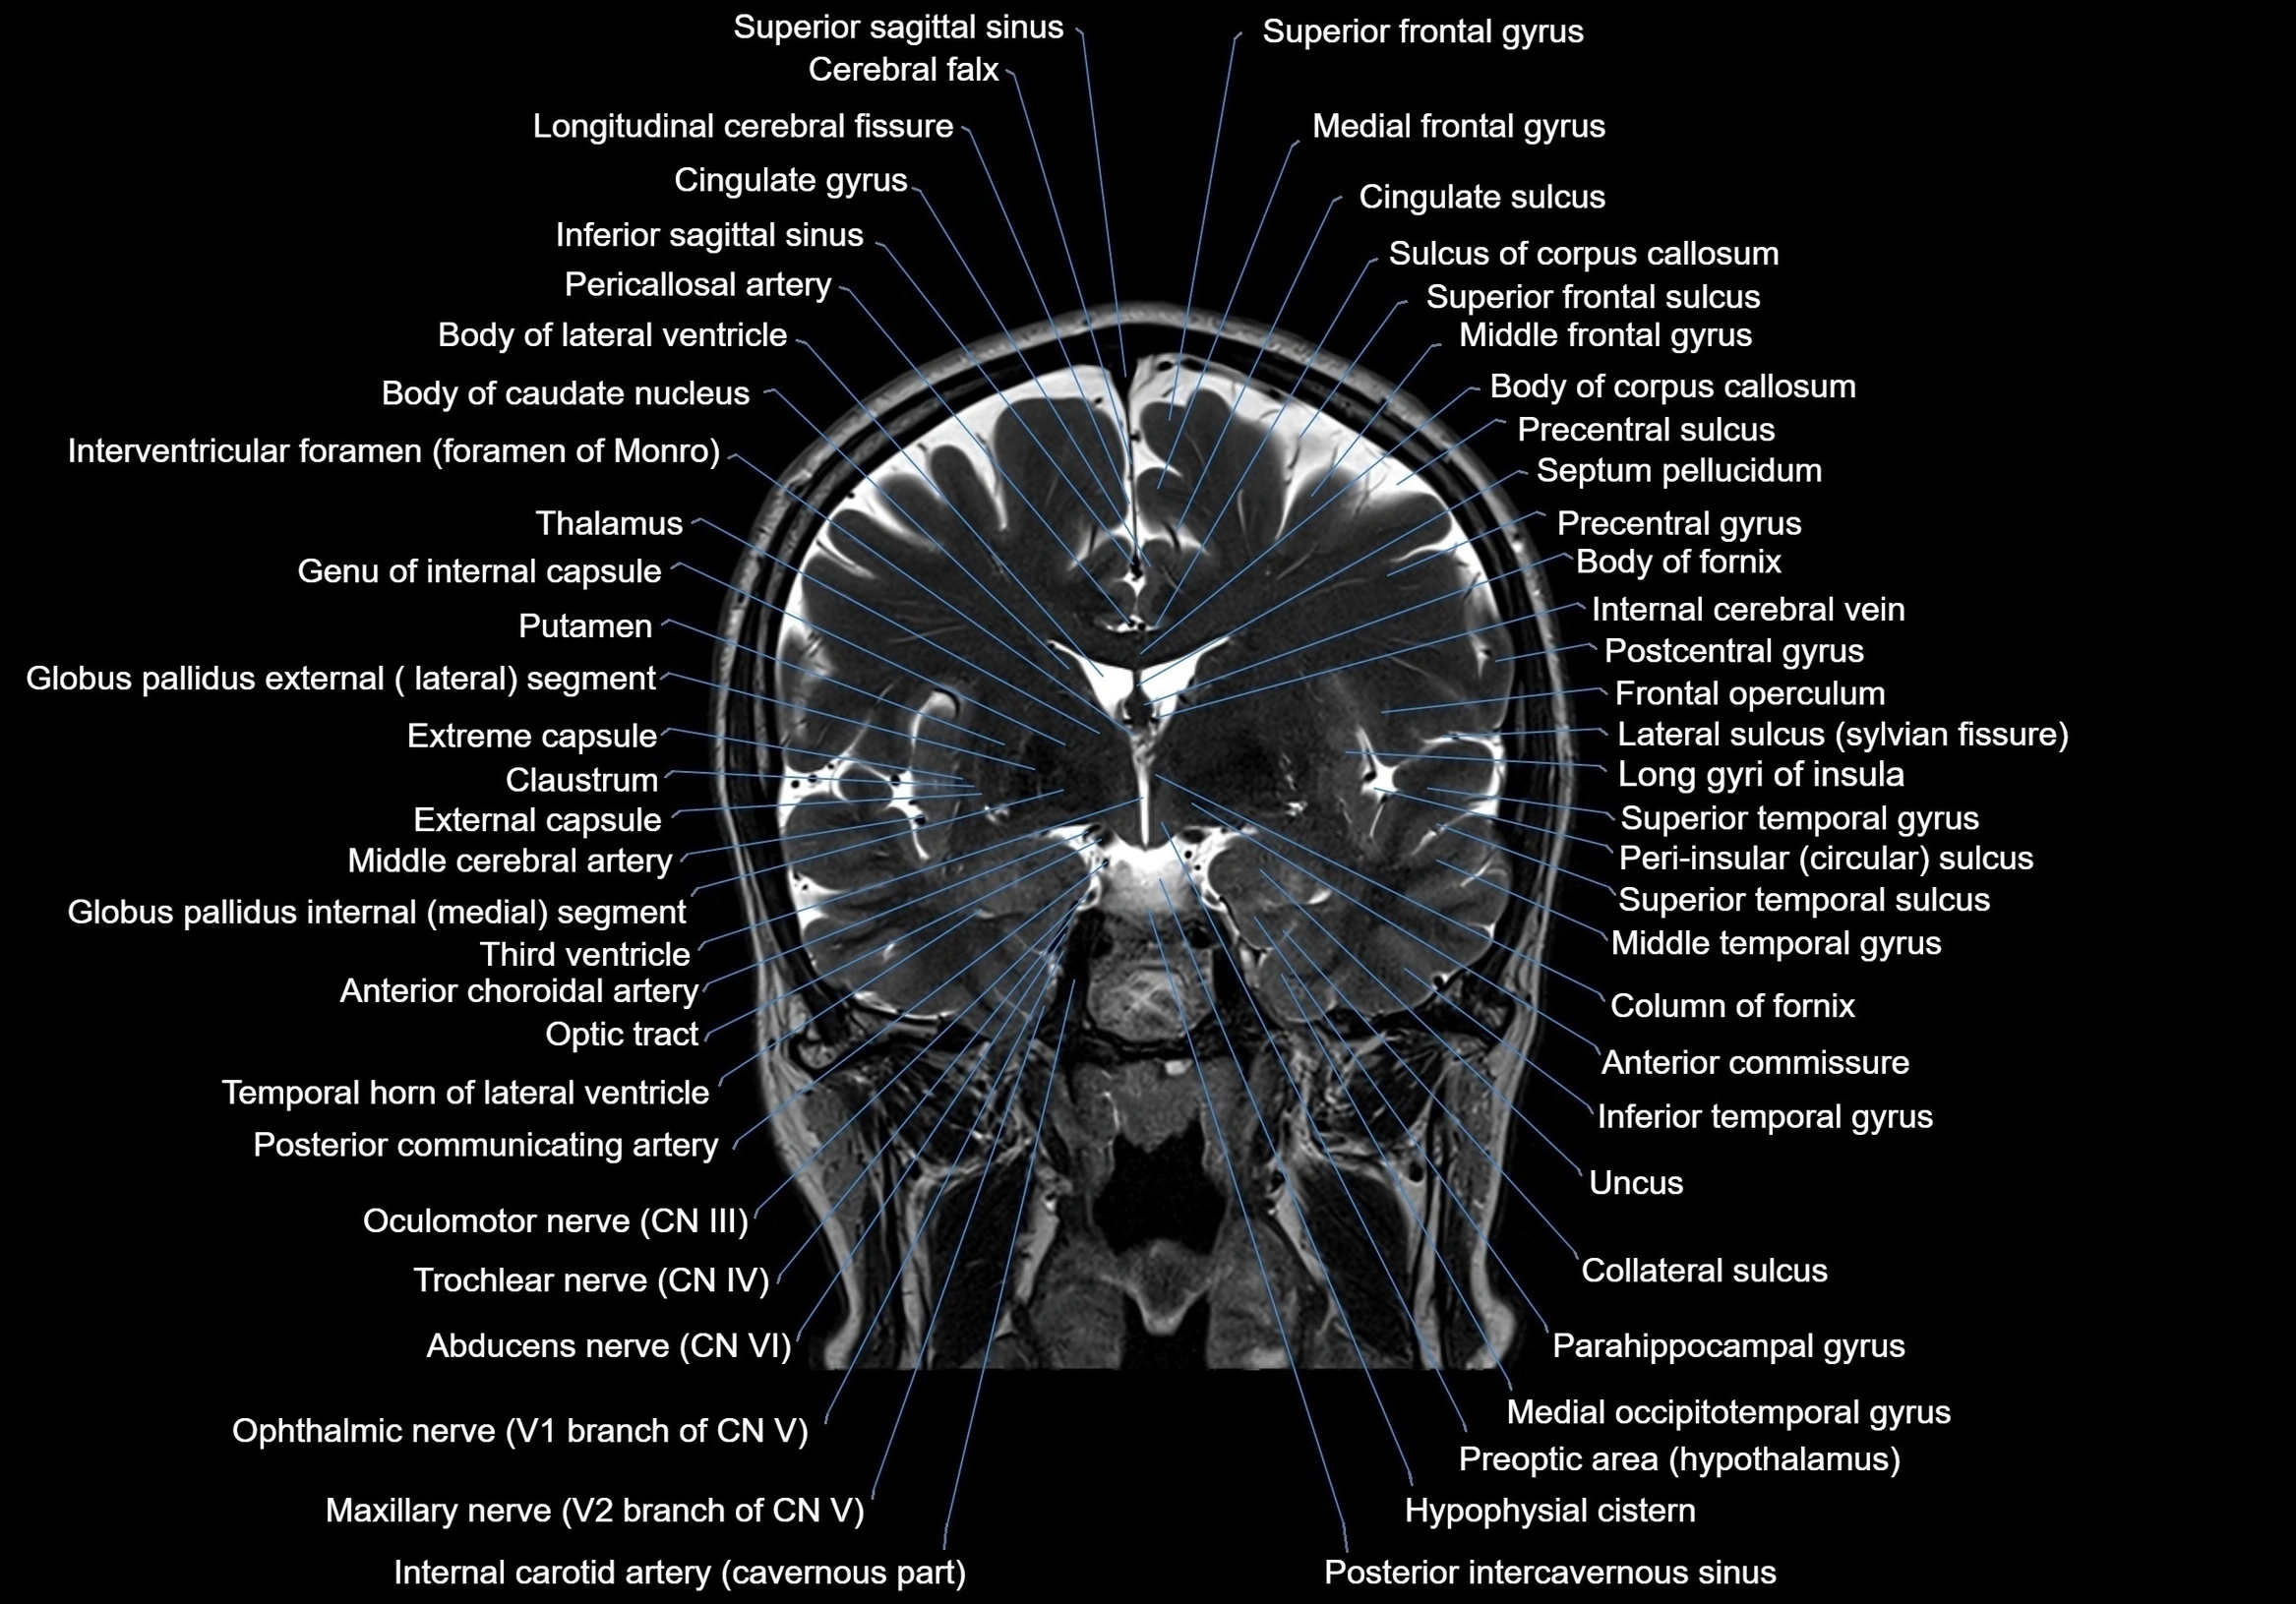

MRI images